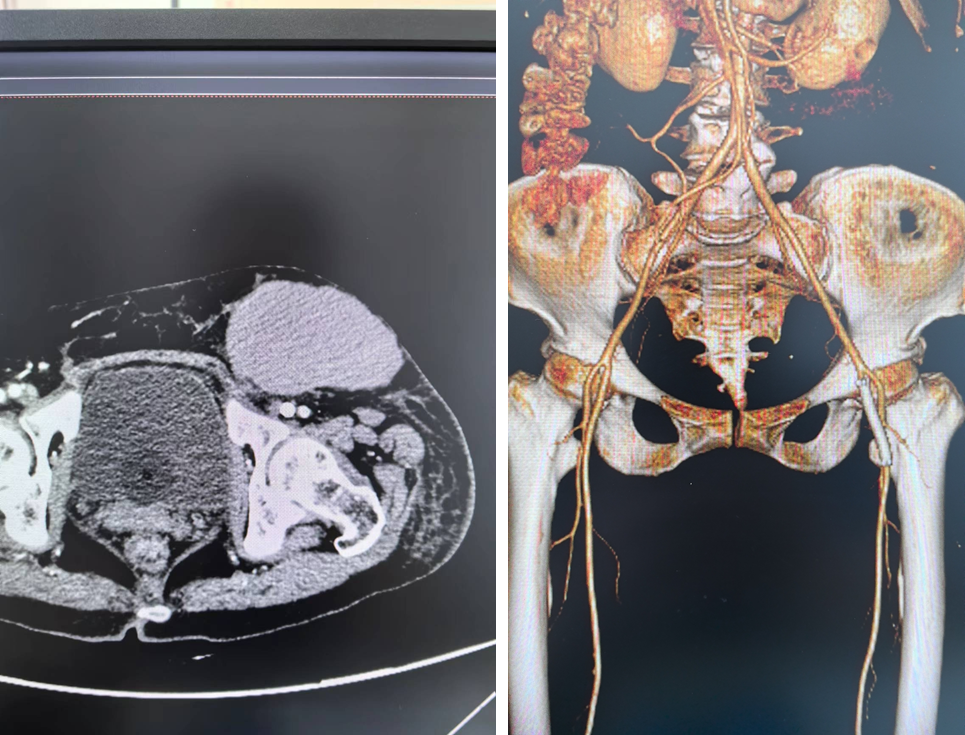

患者尹xx,男性,61岁。1月前无明显诱因发热,外院诊断为“金黄色葡萄球菌性败血症”,同时检查发现右侧股动脉假性动脉瘤,保守治疗后好转出院。1天前突发右侧腹股沟区持续性钝痛,遂来我院就诊。